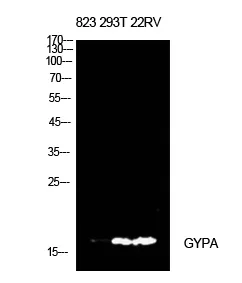

CD235a Rabbit Polyclonal Antibody

Cat: APRab08295

Size1:50μl Price1:$118

Size2:100μl Price2:$220

Size3:500μl Price3:$980